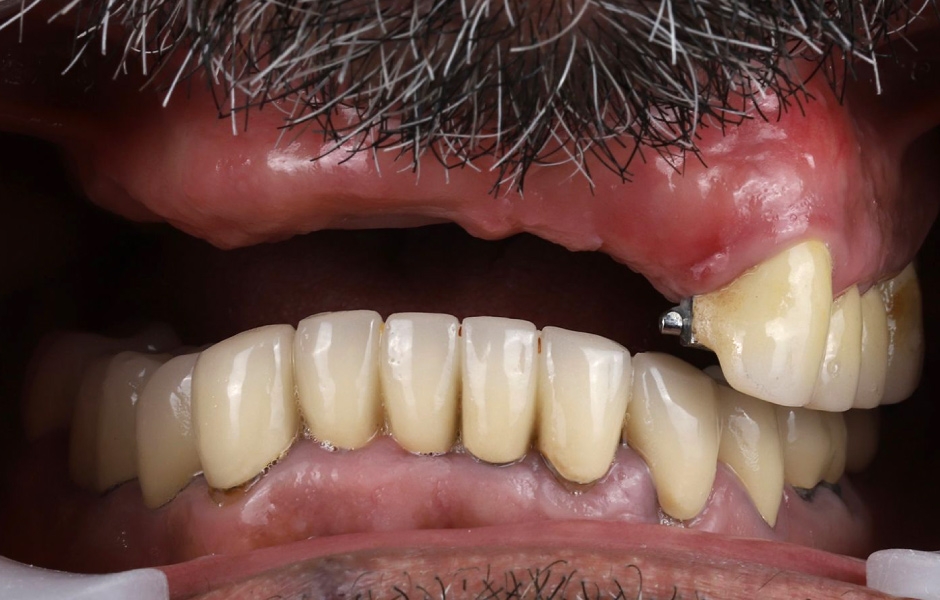

Při extraorální prohlídce nebyly zjištěny žádné významné abnormality. Pacient měl střední úroveň linie úsměvu (obr. 1–3). Po vyjmutí snímatelné náhrady byl odhalen můstek (obr. 4).

Intraorální vyšetření odhalilo starý můstek, který nahrazoval zuby 23 až 26 a zároveň sloužil ke kotvení částečné snímatelné náhrady s kovovou výztuží. Zuby 22 až 17 byly extrahovány již před delší dobou a alveolární hřeben v této oblasti byl zhojen. Nebyl přítomen plak ani zánět. Zuby vykazovaly mírnou až střední ztrátu attachmentu, ale nebyly pozorovány žádné parodontální léze nebo fraktury kořenů (obr. 5–8).

Obr. 3, 4

Obr. 5

Obr. 6

Obr. 7

Obr. 8